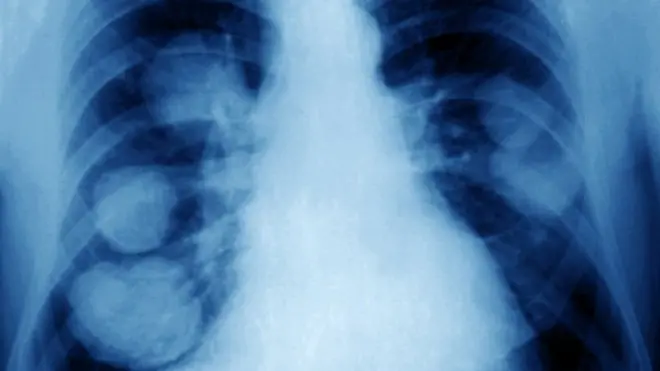

ریو وائرس تھیراپی کے ذریعے کینسر کا علاج ممکن

برطانوی سائنسدان پر امید ہیں کہ انھوں نے دماغ کے ایک ایسے کینسر کا علاج ڈھونڈ لیا ہے جو اب تک لاعلاج تھا۔

یہ علاج ایک وائرس کے ذریعے ممکن ہو سکتا ہے جس کے جسم میں جانے کے بعد ہلکے فلو جیسی علامات سامنے آتی ہیں۔ برطانیہ میں اب تک دس افراد پر یہ طریقۂ علاج آزمایا جا چکا ہے۔

ابتدائی تحقیق کے مطابق یہ وائرس جسم کے دفاعی نظام کو متحرک کر کے اسے دماغ میں موجود ٹیومر کی طرف متوجہ کر دیتا ہے۔ جس کے نتیجے میں یہ دفاعی نظام ٹیومر پر حملہ کر دیتا ہے۔